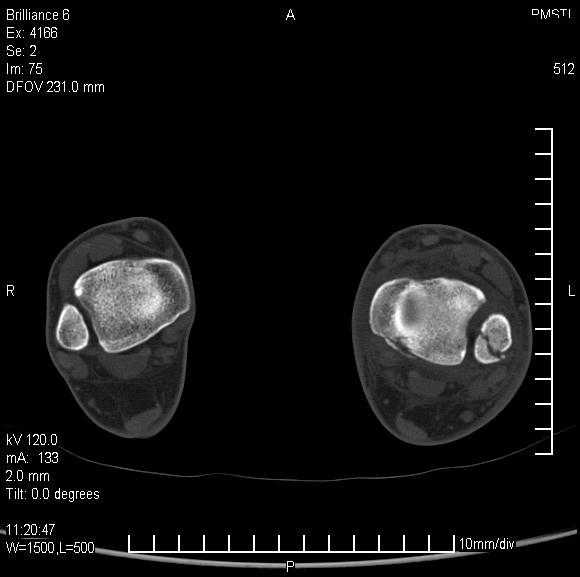

Уважаемые коллеги!Помогите, пожалуйста, советом! Пациентка 14 лет. Двухлодыжечный перелом с (как нам кажется) повреждением межберцового синдесмоза. Вопрос один: оперировать или оставить "как есть" в гипсе? Не будет ли в дальнейшем проблем с суставом. Заранее спасибо.

КТ это очень хорошо. В данной ситуации КТ не помогает а ставит новые вопросы... На мой взгляд проблема в синдесмозе: нужно исключить его расхождени - сделать снимок здоровой конечности. В этом плане МРТ еще круче - при исследовании свежего повреждения коленного сустава всегда найдутся показания к операции.

Уважаемый Сергей! Я не навязываю свое мнение, но по моему, ребенка в данном случае нужно лечить консервативно в гипсовой повязке. Старая мудрость "Хирург славен не теми операциями которые он сделал, а теми от которых он отказался" На мой взгляд по тем снимкам которые представлены, суставная щель по ширине одинакова по всему суставу, значит "вилка" удерживающая таранную кость не разошлась. С уважением Евгений.